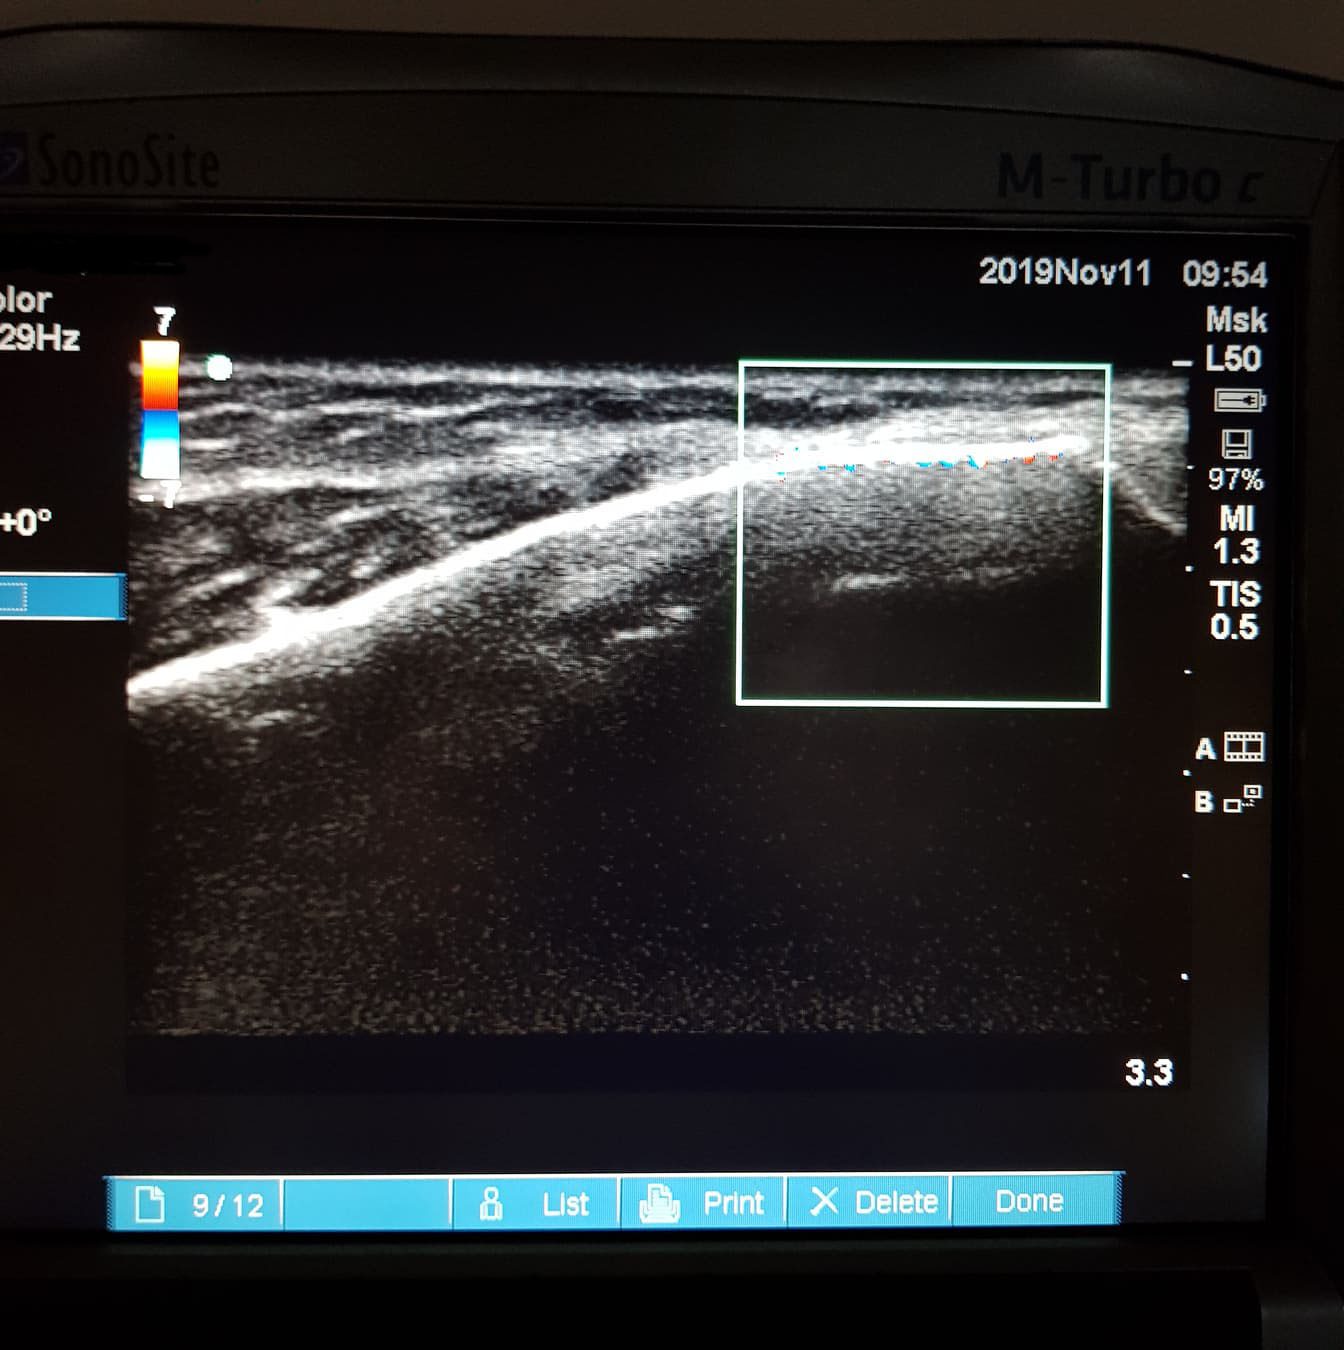

Den rette diagnose stilles ved ultralydsscanning og en grundig klinisk undersøgelse, hvor vi vurderer både symptomer, smerteprovokation og bevægemønster. Særligt timingen af smerterne – hvornår de opstår, og hvad der provokerer dem – giver et præcist billede af, om der er tale om akillessenebetændelse eller en anden tilstand i området.

Hos Snowfun Klinik ser vi mange patienter, der oplever smerter bag på hælen og tror, at årsagen er en hælspore eller irritation i fodens svang. I virkeligheden skyldes generne ofte akillessene-inflammation, som opstår, når senen bliver overbelastet og ikke får tid eller kapacitet til at hele. En korrekt diagnose kræver en grundig klinisk undersøgelse – ofte suppleret med ultralydsscanning, der viser både senens struktur, graden af irritation og eventuelle forandringer i vævet.

Oplever du smerter, hævelse eller rødme bag på hælen – især når du går, løber eller står på tæer – anbefaler vi en grundig fodanalyse og ultralydsscanning. Det giver klarhed over årsagen og gør det muligt at vælge den rette behandling, så du kan vende tilbage til en smertefri og aktiv hverdag.